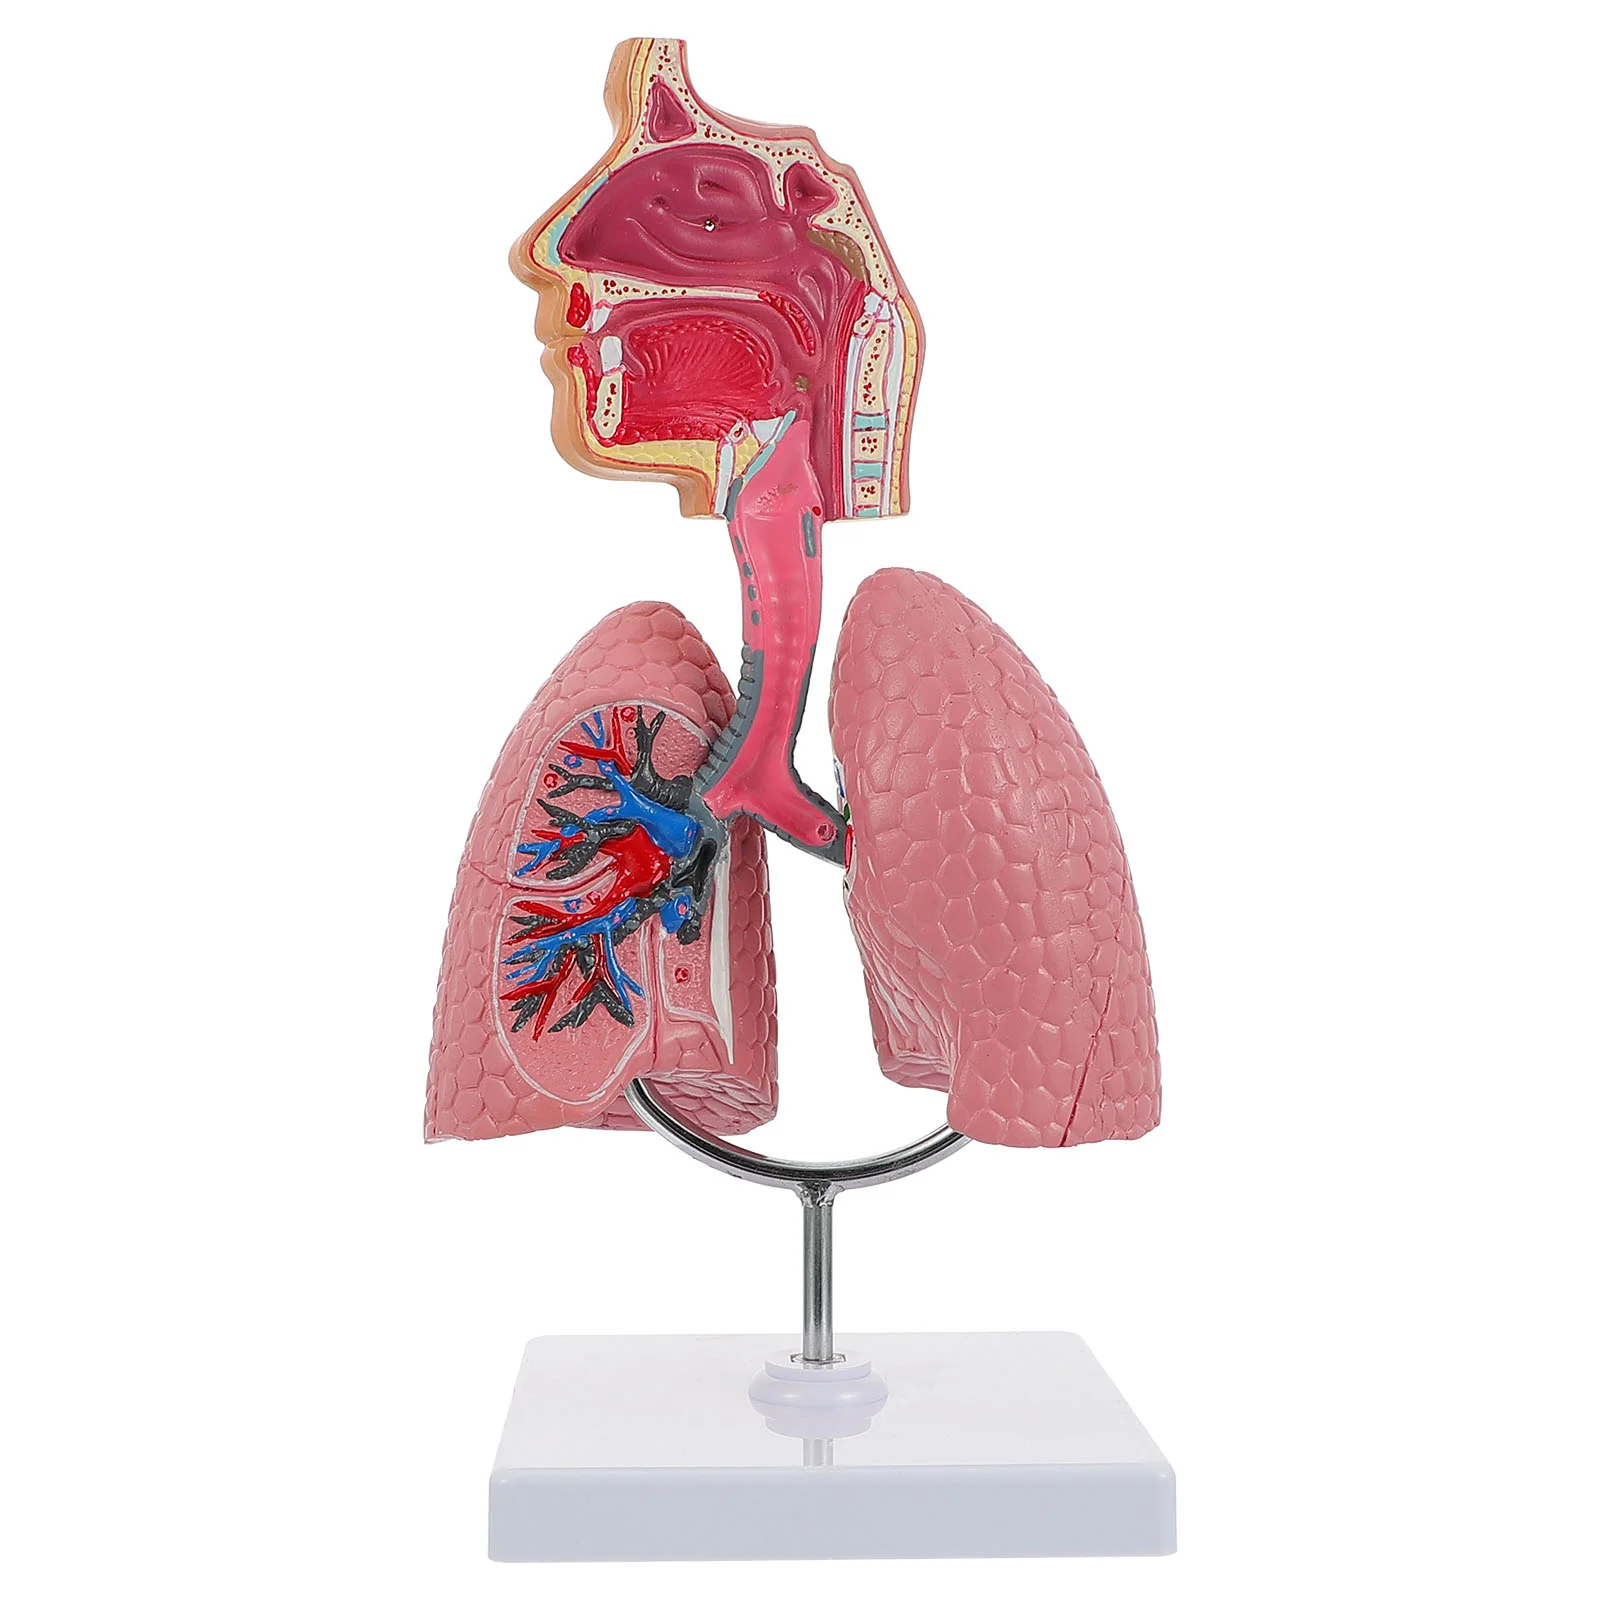

1pc Teaching Respiratory Lung Model School Respiratory System Display Model Tool

aliexpress.com